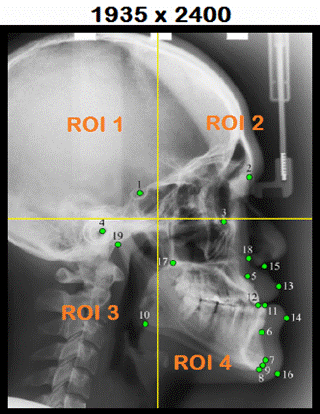

9 Catagories: Cat1=UP, Cat2=DOWN, Cat3=RIGHT, Cat4=LEFT, Cat5=UP-RIGHT, Cat6=UP-LEFT, Cat7=DOWN-RIGHT, Cat8=DOWN-LEFT, Cat9=INSIDE |

Neuromem® Context 1

ROI1, ROI2, ROI3, ROI4: Sub-sampling 16x16 Learn ROI1 = Cat3 Learn ROI2 = Cat9 Learn ROI3 = Cat5 Learn ROI4 = Cat1 SetContext(int

ROI2: Sub-sampling x 2 Neuromem® Context 2

ROI1, ROI2, ROI3, ROI4: Sub-sampling 16x16 Learn ROI1 = Cat7 Learn ROI2 = Cat2 Learn ROI3 = Cat3 Learn ROI4 = Cat9 SetContext(int

ROI4: Sub-sampling x 2 Neuromem® Context 3

ROI1, ROI2, ROI3, ROI4: Sub-sampling 16x16 Learn ROI1 = Cat2 Learn ROI2 = Cat8 Learn ROI3 = Cat9 Learn ROI4 = Cat4 SetContext(int

ROI3: Sub-sampling x 2 Neuromem® Context 4

ROI1, ROI2, ROI3, ROI4: Sub-sampling 16x16 Learn ROI1 = Cat9 Learn ROI2 = Cat4 Learn ROI3 = Cat1 Learn ROI4 = Cat6 SetContext(int

ROI1, ROI2, ROI3, ROI4: Sub-sampling 16x16 Recognize ROI1 => Cat3 Recognize ROI2 => Cat9 Recognize ROI3 => Cat5 Recognize ROI4 => Cat1 SetContext(int

*categories, int *nids); (ROI1==Cat3) &

(ROI2==Cat9) & (ROI3==Cat5) & (ROI4==Cat1) => ROI2 |

ROI1, ROI2, ROI3, ROI4: Sub-sampling 16x16 Recognize ROI1 => Cat7 Recognize ROI2 => Cat2 Recognize ROI3 => Cat3 Recognize ROI4 => Cat9 SetContext(int

*categories, int *nids); (ROI1==Cat7) & (ROI2 ==

Cat2) & (ROI3 == Cat3) & (ROI4 == Cat9) => ROI4 |

ROI1, ROI2, ROI3, ROI4: Sub-sampling 16x16 Recognize ROI1 => Cat2 Recognize ROI2 => Cat8 Recognize ROI3 => Cat9 Recognize ROI4 => Cat4 SetContext(int

*categories, int *nids); (ROI1==Cat2) &

(ROI2==Cat8) & (ROI==Cat9) & (ROI4==Cat4) => ROI3 |

ROI1, ROI2, ROI3, ROI4: Sub-sampling 16x16 Recognize ROI1 = Cat9 Recognize ROI2 = Cat4 Recognize ROI3 = Cat1 Recognize ROI4 = Cat6 SetContext(int

*categories, int *nids); (ROI1==Cat9) &

(ROI2==Cat4) & (ROI==Cat1) & (ROI4==Cat6) => ROI1 |

L2 (Nasion) RESEARCH FOCUS PATH